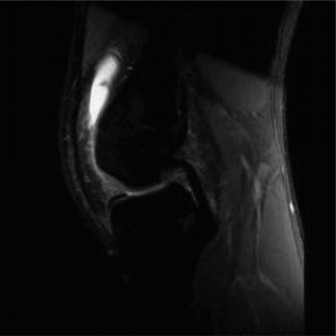

Following the plain radiographs, an urgent Magnetic Resonance Imaging study of the entire right femur with and without intravenous gadolinium contrast was executed to delineate the exact anatomical extent of the lesion.

The MRI protocols included T1-weighted, T2-weighted fat-suppressed (STIR), and T1 post-contrast sequences. The T1-weighted coronal sequences were critical for mapping the intramedullary extent of the tumor, which replaced the normal high-signal fatty marrow with intermediate-signal tumor tissue. The tumor measured 11.5 centimeters in craniocaudal dimension. Crucially, the MRI confirmed that the distal extent of the tumor abutted, but did not frankly cross, the open distal femoral physis.

Axial T2-weighted sequences demonstrated a large, heterogeneous, hyperintense extraosseous soft tissue component. The neurovascular bundle (popliteal artery and vein) was displaced posteriorly but maintained a visible fat plane, indicating it was not directly encased by the tumor—a vital finding for potential limb salvage. Whole-bone imaging confirmed the absence of intramedullary "skip" metastases.